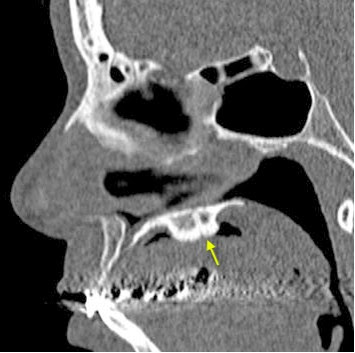

Sagital Janela Óssea. A célula agger nasi (asterisco) promove aparente efeito compressivo com afilamento do compartimento inferior de drenagem do seio frontal (seta). Este é um caso em que na nossa avaliação a variante anatômica tem que ser relatada, ainda que a relação causa-efeito desta variante com eventual rinossinusopatia continue sendo uma hipótese.

Coronal Janela Óssea. Células etmoidais anteriores que se projetam anteriormente. Células agger nasi (Seta).